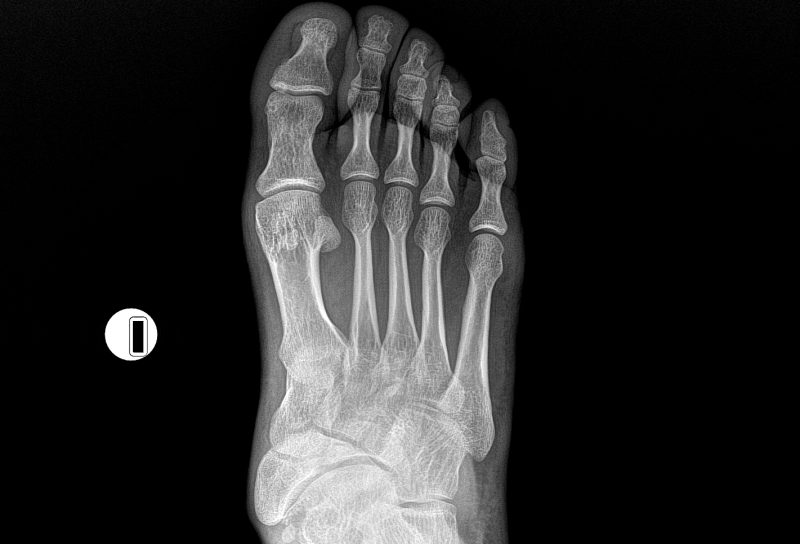

El servicio de Rayos X, se encarga de realizar estudios radiográficos para obtener imágenes del interior del cuerpo humano mediante radiación ionizante. Estas imágenes permiten observar estructuras óseas y algunos tejidos blandos, facilitando el diagnóstico médico de fracturas, infecciones, alteraciones pulmonares, entre otras patologías.

El Hospital CEMA cuenta con personal especializado y equipos digitales que garantizan calidad diagnóstica y seguridad del paciente.